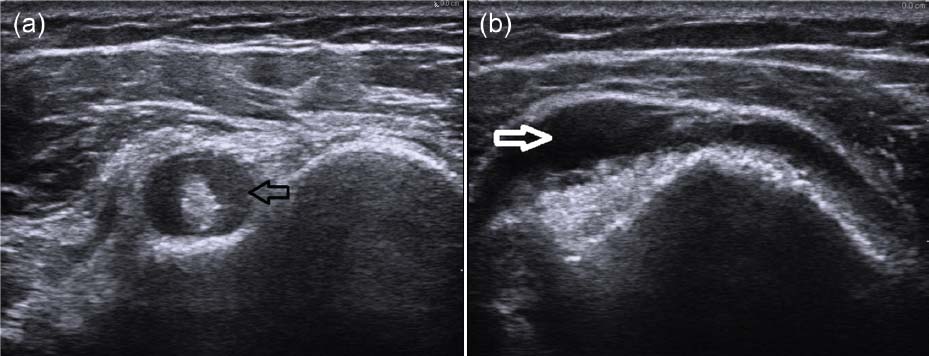

血液検査では赤沈値の亢進やCRPの上昇など炎症反応を認める。リウマトイド因子、抗CCP抗体、抗核抗体といった自己抗体は通常陰性で、CK、アルドラーゼなどの筋原性酵素は正常である。超音波やMRI(magnetic resonance imaging)検査では、両側の肩峰下や三角筋下、大腿骨大転子下に滑液包炎を高頻度に認める。

二頭筋腱滑膜炎(短軸像)(a)および三角筋下滑液包炎(b)を示すリウマチ性多発筋痛症患者2名の肩の超音波検査所見。

Ther Adv Musculoskel Dis 2014, Vol. 6(1) 8-19